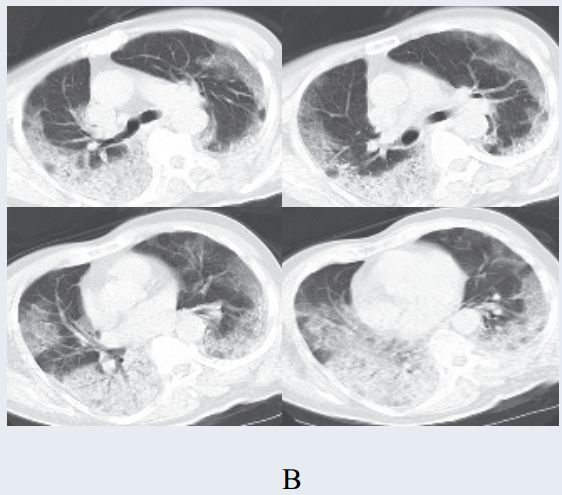

二、进展期征象

新冠肺炎大多数病例进展迅速,复查 CT 影像发生明显变化。

表现为病灶数目明显增多,范围明显扩大,密度增高,病灶分布由外周向中央推进。

根据既往 SARS 病理学机制,提示为肺泡腔内聚集大量细胞渗出液、间质内血管扩张渗出;肺泡连通起来形成融合态势(图 2-11)。

图 2-11 病灶数目增多、范围扩大 (A-D)